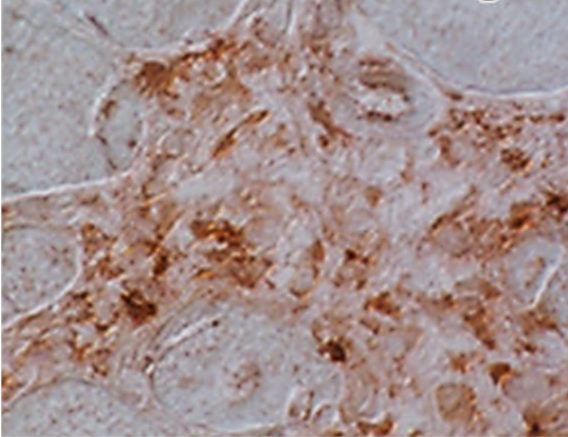

IHC-Fr analysis of mouse muscle tissue using GTX53209 Klotho antibody [4F54].